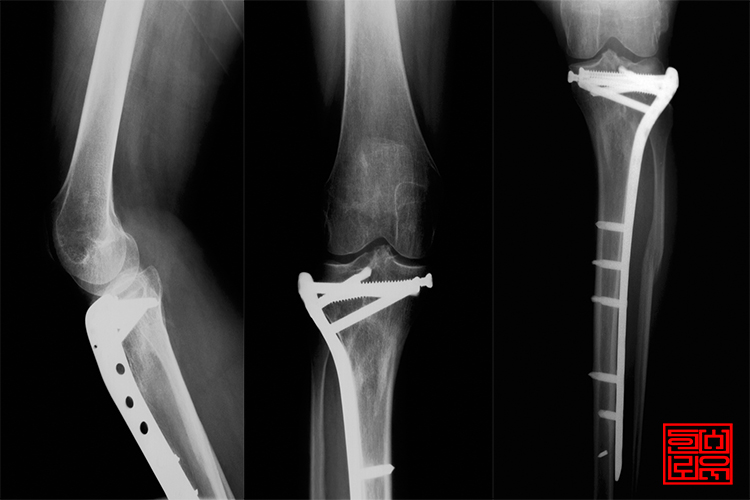

°ñÀý ¹× »óÇØ·Î Ä¡·áÈÄ ³²Àº ÀåÇØ¿¡ ´ëÇÑ º¸Çè±Ýû±¸